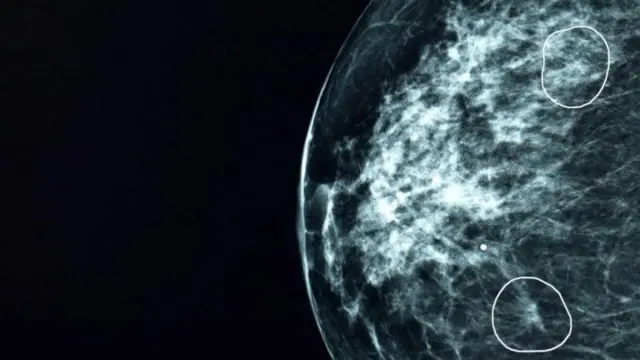

10 వేల మందికి పైగా మహిళల మామోగ్రామ్లను మియా పరీక్షించింది. మామోగ్రామ్ అనేది రొమ్ము క్యాన్సర్ లక్షణాలు లేదా సంకేతాలు లేని మహిళల్లో ఈ వ్యాధి ఉందో లేదో గుర్తించేందుకు ఉపయోగించే ఎక్స్-రే పిక్చర్.

వీరిలో చాలా మందికి ఎలాంటి క్యాన్సర్ లక్షణాలు లేవని వైద్యులు గుర్తించారు. కానీ, వైద్యులు గుర్తించలేని క్యాన్సర్ లక్షణాలను 11 మంది రోగుల్లో మియా విజయవంతంగా గుర్తించింది.

ప్రాథమిక దశల్లో క్యాన్సర్ ట్యూమర్లు చాలా చిన్నగా ఉండి, వాటిని గుర్తించడం కష్టంగా ఉంటుంది.

మనిషి కంటికి కనిపించని ఇలాంటి ట్యూమర్లను సింథటిక్ టెక్నాలజీ టూల్ ‘మియా’ కచ్చితత్వంతో గుర్తించగలదు. ఈ ట్యూమర్లు వాటి రకాన్ని బట్టి వేగంగా వృద్ధి చెంది, విస్తరిస్తాయి.

ఎందుకంటే బార్బరా ట్యూమర్ పరిమాణం 6 ఎంఎంగా ఉంది. మియా టూల్ ద్వారా చాలా త్వరగా ఈ ట్యూమర్ను గుర్తించడంతో ఆమెకు ఆపరేషన్, ఐదు రోజుల రేడియోథెరపీ చికిత్సతో సరిపోయింది.

15ఎంఎం కంటే చిన్నగా ఉన్నప్పుడే ట్యూమర్లను గుర్తిస్తే వచ్చే ఐదేళ్లలో సర్వైవల్ రేటు(బతికే అవకాశం) 90 శాతంగా ఉంటుంది.